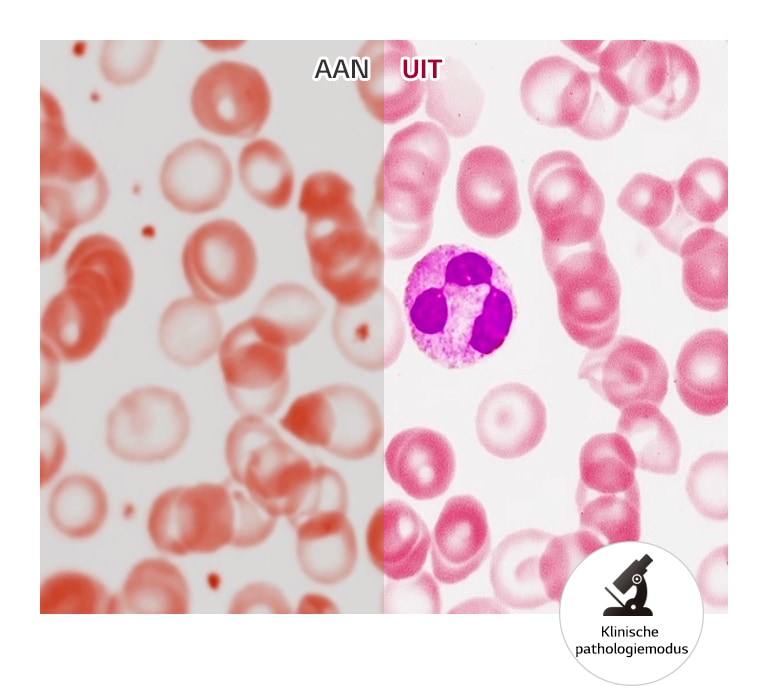

Pathology Mode

JA